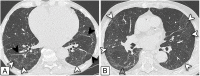

Results: At a median of 105 days from symptom onset, 74/91 (81 %) patients had CT abnormalities. The most common CT pattern was combined ground-glass opacity and reticular pattern (46/74, 62 %) along with architectural distortion (68/74, 92 %) and bronchial dilatation (66/74, 89 %). Compromised lung volume had a median value of 15 % [11-23], was higher in dyspneic patients, and negatively correlated with the percentage of predicted DLCO, VA, and FVC values (r = -0.39, -0.5, and -0.42, respectively). These PFT parameters were significantly lower in patients with CT abnormalities. Impairment of DLCO and KCO was found in 12 (13 %) cases, possibly implying an underlying pulmonary vasculopathy in this subgroup of patients.